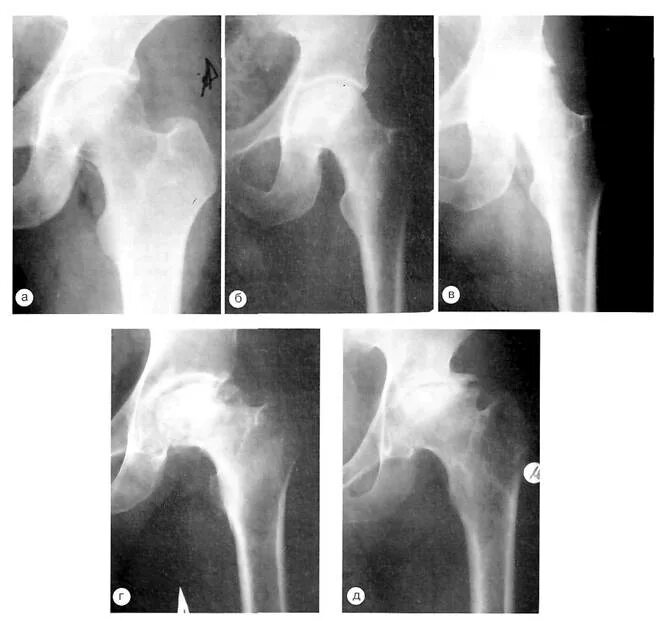

Обследование тазобедренного сустава